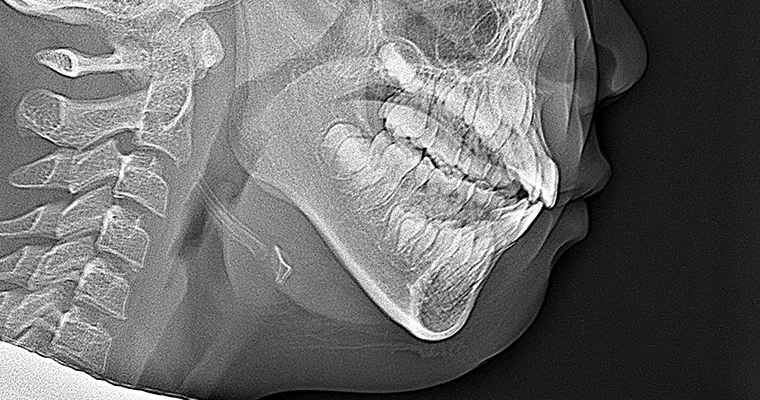

治療前 パノラマレントゲン

治療前 セファロレントゲン

| 主訴 | 幼少期から反対咬合 |

|---|---|

| 治療期間 | 10ヶ月 |

| 治療費 | 440,000円(税込) ※調整、器具、治療後にお渡しするEFLine(矯正後の後戻りを防ぐ器具)も全て込みでの金額となっております。 |

| 治療内容 | 6歳で上下拡大 上顎牽引装置 EF Lineで筋機能療法 |